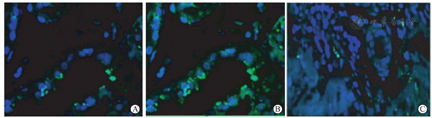

为明确患者皮肤浸润淋巴细胞是否存在供者来源可能,我们进一步对患者皮肤组织内供者特异性抗原HLA-A11抗体(abcam,货号:ab31574)进行免疫荧光染色。获取患者皮损处皮肤组织,切片脱蜡,柠檬酸缓冲液加热抗原修复,1%牛血清蛋白(bovine serum albumin, BSA)封闭后经HLA-A11抗体4 ℃孵育过夜,使用磷酸缓冲盐溶液(phosphate buffer saline, PBS)漂洗三次,再使用异硫氰酸荧光素(fluorescein isothiocyanate, FITC)标记山羊抗小鼠IgG(Servicebio,货号:GB22301)和CY3标记山羊抗小鼠IgG(Servicebio,货号:GB21301)荧光二抗室温同时孵育1小时,PBS漂洗三次,4’,6-二脒基-2-苯基吲哚(4’,6-diamidino-2-phenylindole, DAPI)染核1分钟后封片,通过荧光显微镜镜下观察获得数据。

皮肤活体组织检查与外周血嵌合体检测结果出现的矛盾,对患者疾病的确诊和进一步治疗带来困惑。经过仔细对比供受者HLA抗原差异,对皮肤病理切片进行了针对供者来源特异性HLA-A11抗原免疫荧光染色。荧光染色结果显示,患者皮肤组织中大量侵润淋巴细胞为供者特异性来源(图4A、图4B、图4C)。综合上述结果,我们最终成功确诊该患者为GVHD。因患者未出现腹泻等胃肠道不适等症状,患者不同意行胃肠道活体组织检查。